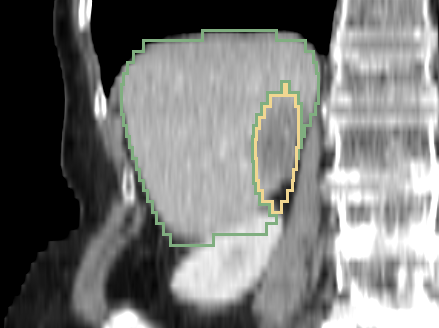

Appendix B Liver Tumor Segmentation Challenge

We show 9 example sagittal slices from the LITS challenge test set in Fig. 23 to demonstrate the variation of both livers and liver lesions. The images are cropped to the region with liver centered. The sizes and shapes of the livers vary a lot between individuals. The variation of liver lesion in sizes and intensities is even higher. The lesions are highly sparse in the abdominal CT images. Thus it is challenging for the networks to segment the lesions with small sizes. Please note that we do not have the ground truth of the test volumes.

Three example volumes are selected from the test image set to demonstrate the effectiveness of our proposed network in Fig. 24, Fig. 25 and Fig. 26. Although we do not have the groundtruth label maps for the testing images, the liver boundaries and the presence of lesions can be visually inspected. The liver lesions normally appear as a dark region within the liver. Without sufficient 3D context, MC-GCN tends to generate false positive regions at the structure boundaries, especially under low image contrast. From the sagittal and coronal views, it is visible that MC-GCN could not generate the correct boundaries close to the top or the bottom of the lesion. By considering the consistency between slices, 3D AH-Net can segment the structures in 3D correctly, although the feature extraction network is transferred from a 2D network. The jagged boundary in the sagittal and coronal view is due to the low resolution in the z direction.

Refer to caption

Figure 23: Example sagittal view slices from the LITS challenge test volumes overlaided with the segmentation boundaries obtained with 3D AH-Net. The livers and the lesions both vary in sizes, morphology and intensities.